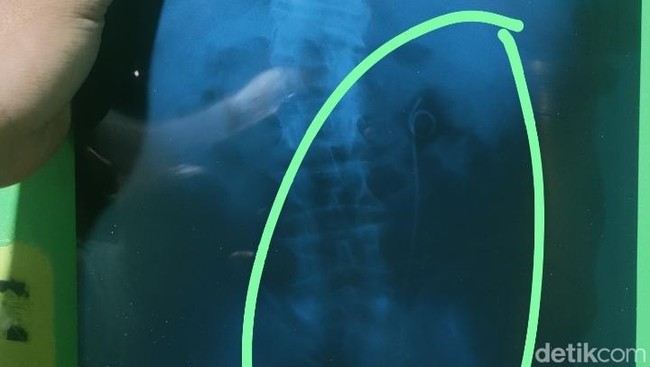

Penampakan selang yang disebut tertinggal di tubuh pria Batang, Jumat (26/9/2025).(Foto: Robby Bernardi/detikJateng)

Melihat foto rontgen yang dibagikan Mistono, selang berukuran panjang 15 sentimeter itu penampakannya mirip selang DJ Stent.

Menurut laman Universitas Airlangga, double J stent (DJ stent) adalah alat yang dipasang pada saluran kemih. Alat berbentuk selang kecil ini biasanya dipasang pada ginjal, ureter, dan kandung kemih untuk melancarkan aliran urin dari ginjal sampai turun ke kandung kemih.